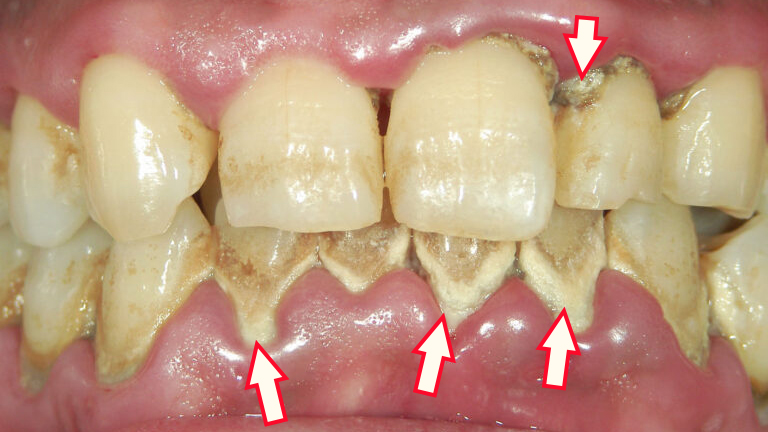

🔥 歯茎の腫れ・赤み・裂開

手遅れの歯周病では、歯茎が赤く腫れあがり、不整形に膨らんだ状態になります。特に黒や白の歯石が沈着した周辺では、炎症が強く、裂けるように歯肉が裂開することもあります。見た目だけでなく、ブラッシング時の痛みや違和感も深刻です。

歯周病は見た目でもある程度の進行度が分かります。とくに重度や末期の症状は、肉眼でも明らかな変化が現れ、セルフチェックの手がかりにもなります。ここでは“手遅れ”とされる状態に見られる特徴的な3つのサインを紹介します。

🖼 歯茎が大きく腫れている

重度の歯周病では、歯茎全体が丸く盛り上がったように腫れあがることがあります。腫れの色は暗赤色〜紫色になり、触るとブヨブヨして痛みや出血を伴う場合も。

- 黒い歯石の周辺:不整形な腫れ+裂け目(裂開)がある

- 白い歯石の周辺:歯茎が丸く、大きく膨らんでいる

- 下前歯・上奥歯:歯石の沈着と合わせて腫れやすい部位

このような腫れは、炎症が歯茎の奥深くまで達しているサインであり、末期の歯周病の典型的な外観です。

🧫 黒い・白い歯石が大量に沈着している

歯周病が長期間放置されると、歯と歯茎の境目に黒色や白色の硬い歯石が大量に付着します。特に下前歯や上奥歯に多く見られ、視診で明らかに確認できます。

- 黒い歯石(縁下歯石):歯周ポケットの奥にでき、重度の炎症の原因に

- 白い歯石(縁上歯石):歯の表面に付着し、目立つことが多い

歯石はバイオフィルムと呼ばれる細菌の塊と共に存在し、自己流の歯磨きでは除去できません。これらが**“手遅れ”の見た目の決定打**になることも多いため、視覚的サインとして非常に重要です。